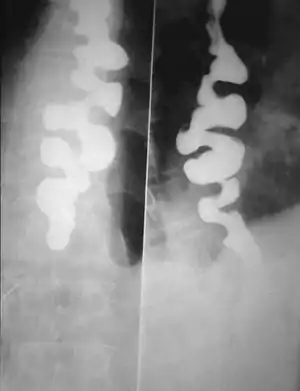

A barium swallow showing a corkscrew appearance due to distal esophageal spasm

Several radiographic findings are suggestive of DES, such as a "corkscrew esophagus" or "rosary bead esophagus" appearance on barium swallow x-ray, although these findings are not unique to DES.[4]